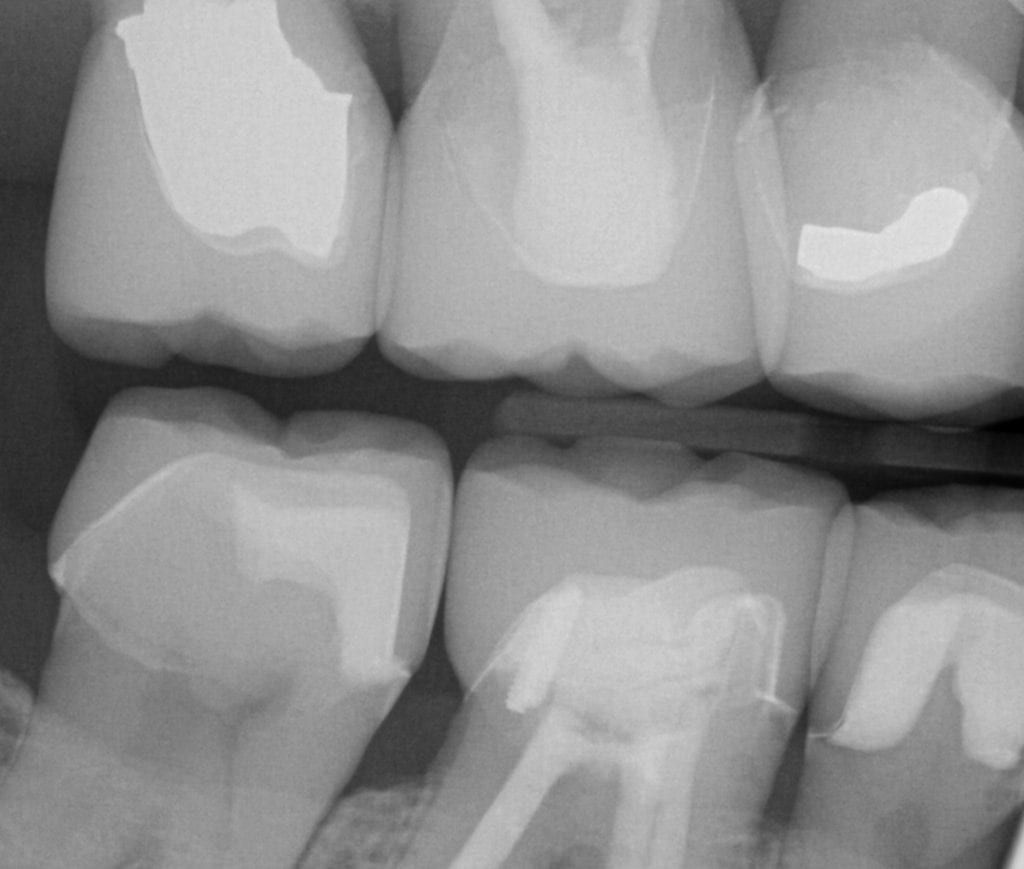

ONE WEEK POST-OP RADIOGRAPHS / CEMENT CHECK